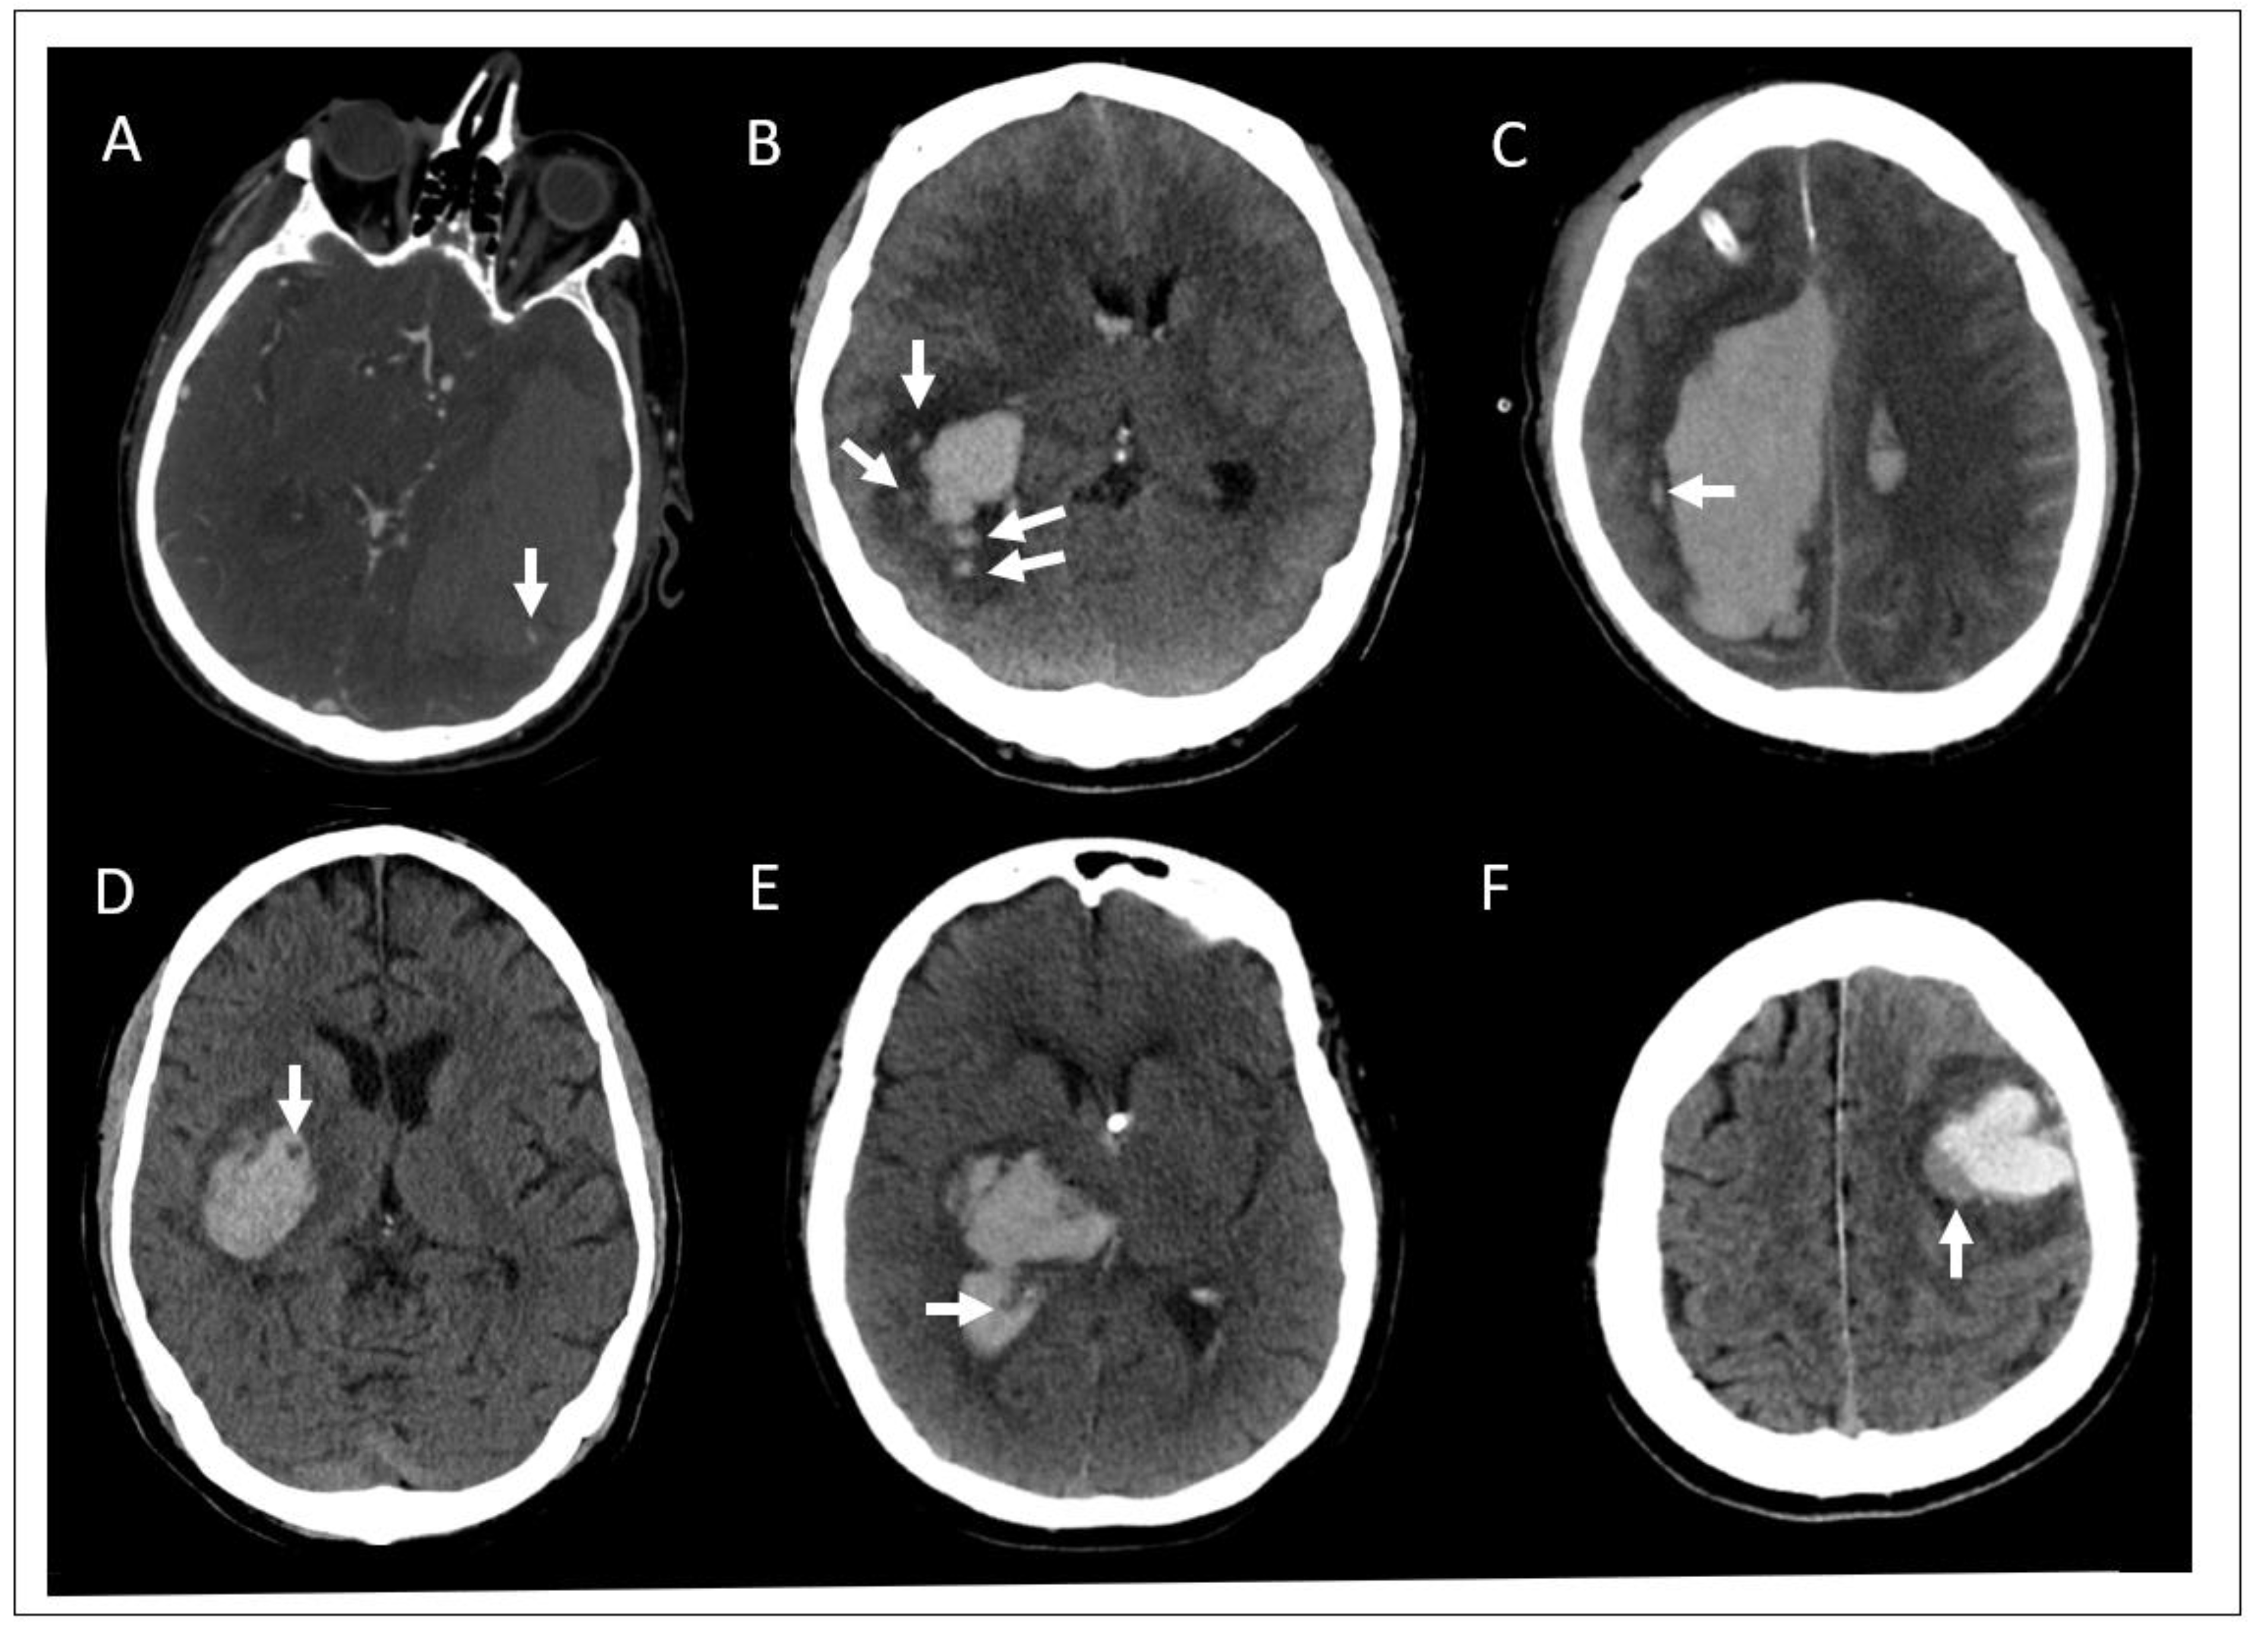

Diagnostics Free Full Text Minimally Invasive Intracerebral Hemorrhage Evacuation Techniques A Review Html